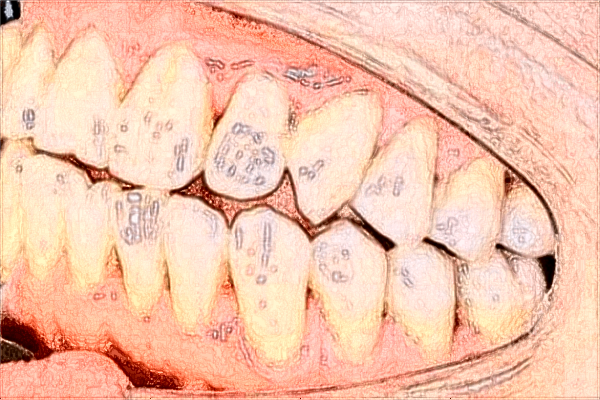

常德市第一人民医院口腔科正畸案例

我的牙齿有一些龅牙,看上去不是特别漂亮,小时候就存在这样的现象,因此小朋友们还给我起了一个外号叫龅牙妹,每次听到这个名字的时候都是很苦恼的,不过自己又是龅牙的状态,的确符合这个名字,慢慢的也接受了现实,长大之后有了这样的能力,第一时间想到的就是通过美容整形的方法来,于是去了常德市第一人民医院口腔科之后医生说需要做正畸,然后医生就给我做了牙齿正畸,在刚开始的时候有一些疼痛,但是这种疼痛感可以承受,戴上牙套大约半年左右的时间,我的牙齿就变得很整齐了,不过医生说还需要继续的牙套,如今已经过去将近两年的时间了,前段时间刚刚摘除了牙套,照了镜子之后,我的牙齿很整齐。